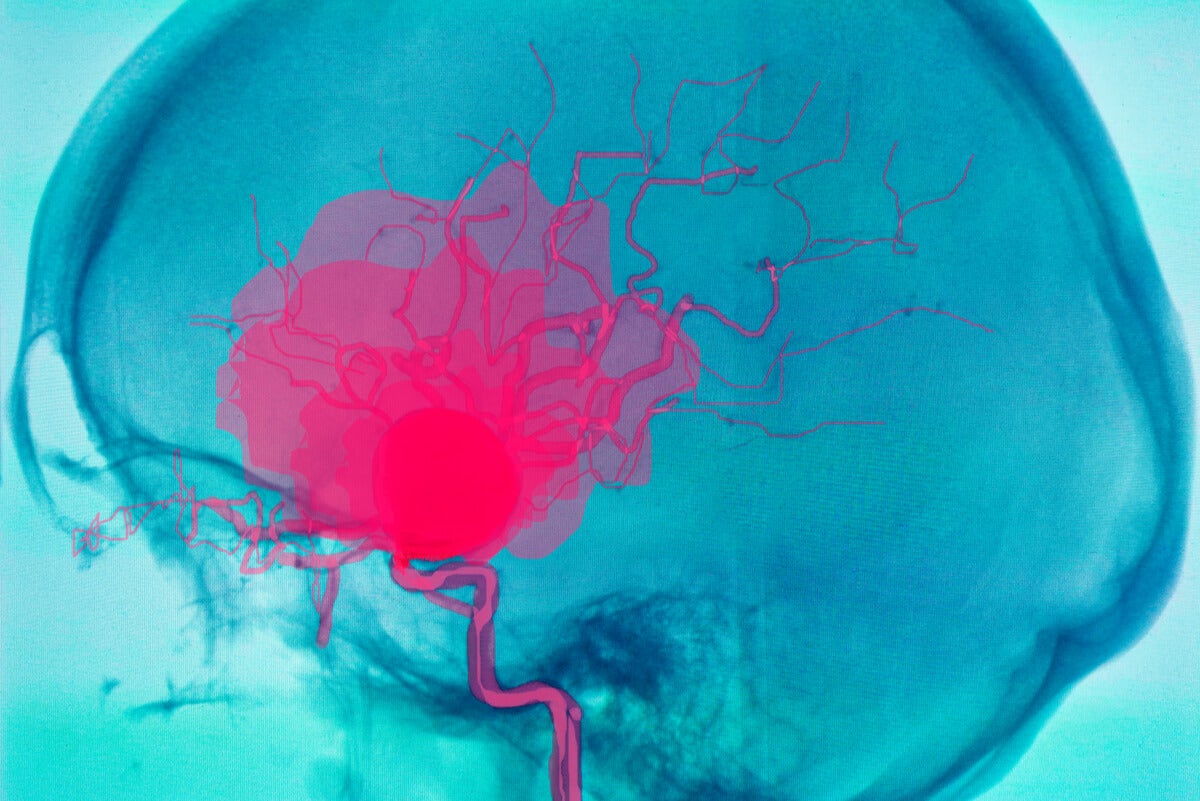

hemorragia cerebral Puede deberse a un trauma cerebral. The following 2 files are in this category, out of 2 total. Media in category intracerebral hemorrhage. La causa suele ser la hipertensión. Puede ser externo o dentro del cuerpo. Como ya se ha mencionado, suele estar relacionada con la hipertensión. Un hematoma intracraneal es una acumulación de sangre dentro del cráneo. En general, se distinguen entre hemorragias profundas (incluyendo aquellas que afectan a núcleos grises profundos de los hemisferios cerebrales), hemorragias.

Cefalea Hemorragia Cerebral Accidente Cerebrovascular Imágenes Del

Source: www.istockphoto.com